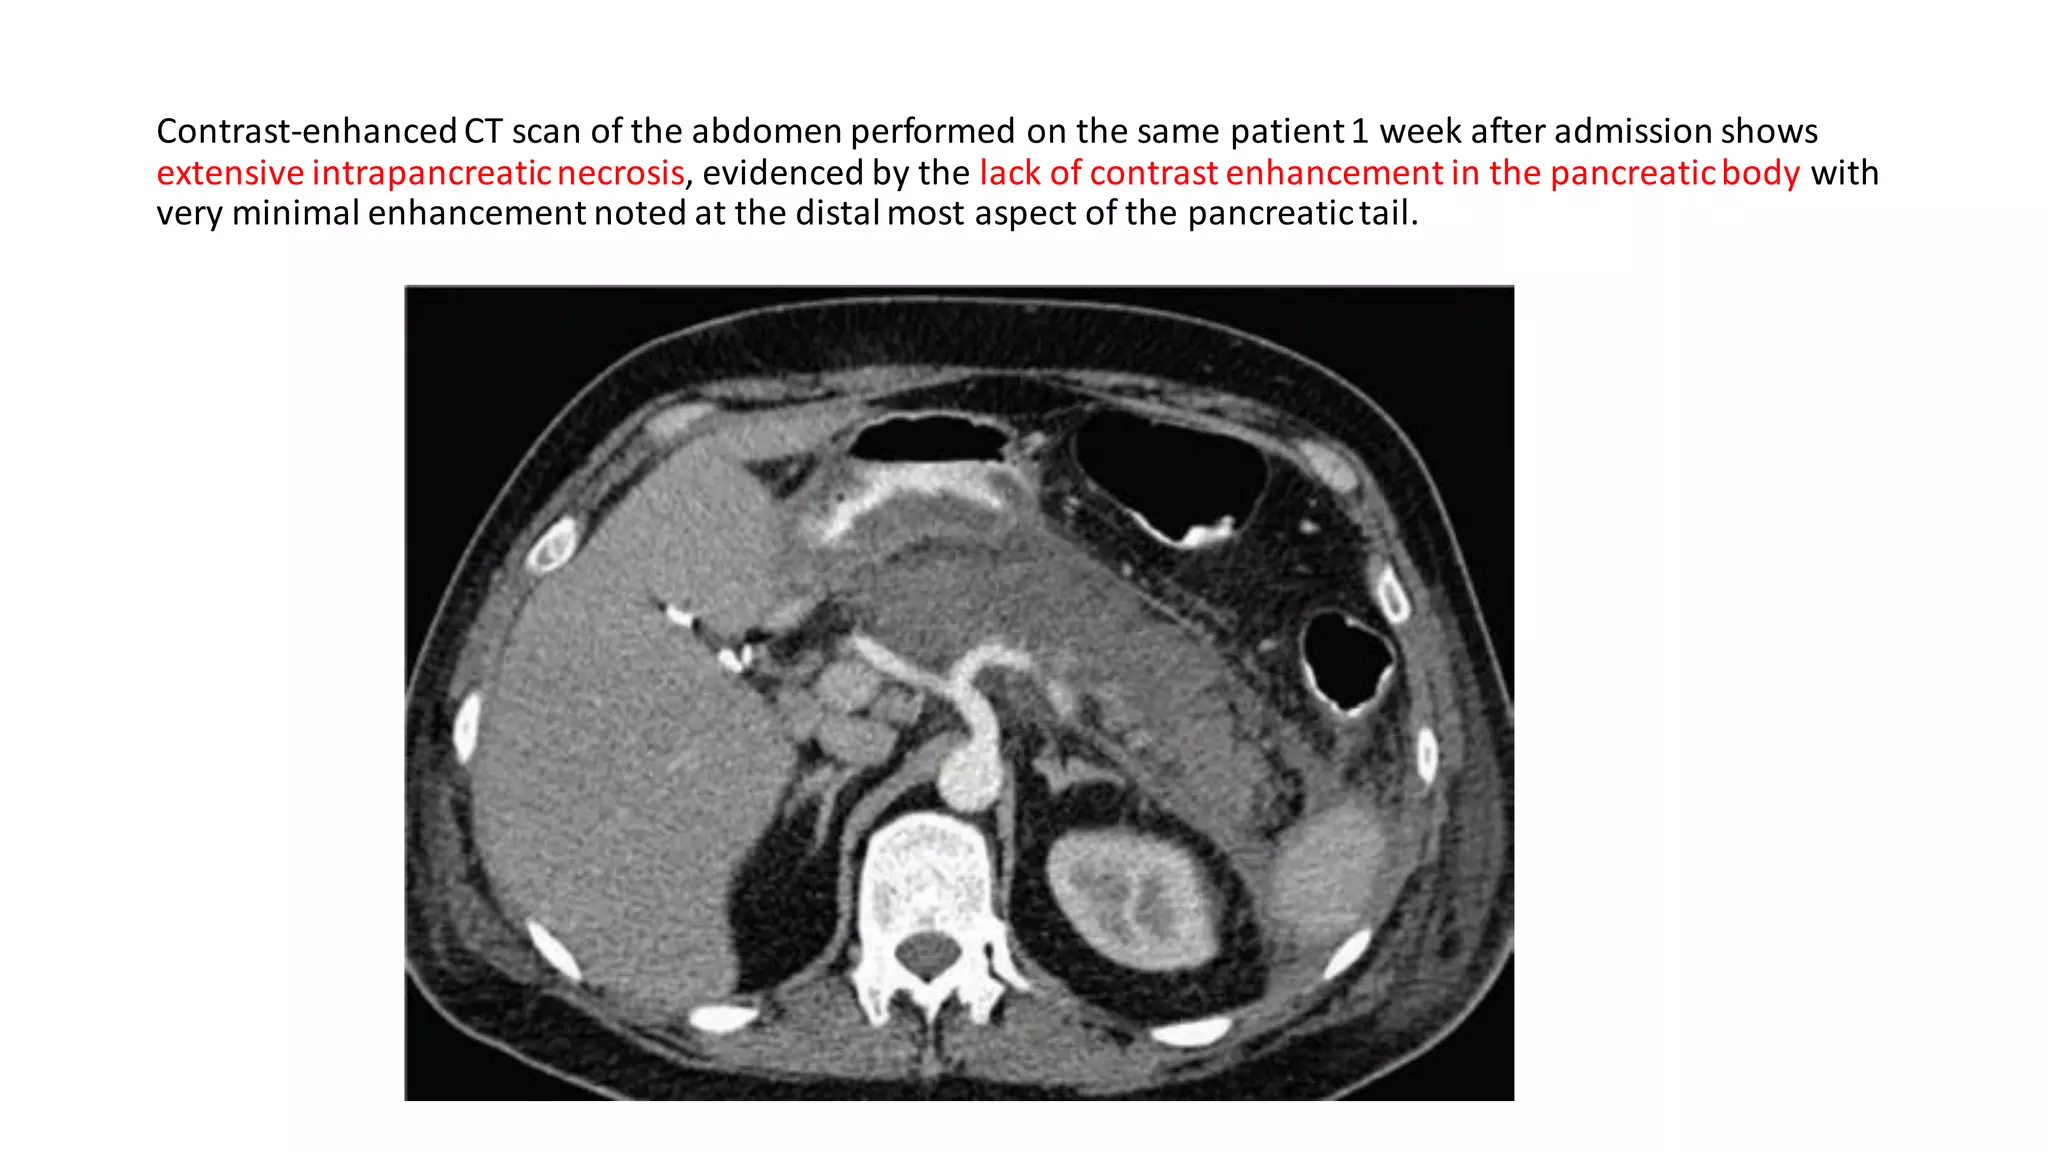

Contrast-enhancedCT scan of the abdomen performed on the same patient1 week after admission shows

extensive intrapancreaticnecrosis, evidenced by the lack of contrast enhancement in the pancreaticbody with

very minimal enhancement noted at the distalmost aspect of the pancreatictail.

Contrast-enhancedCT scan ofthe abdomen performed on the same patient1 week after admission shows extensive intrapancreaticnecrosis, evidenced by the lack of contrast enhancement in the pancreaticbody with very minimal enhancement noted at the distalmost aspect of the pancreatictail.